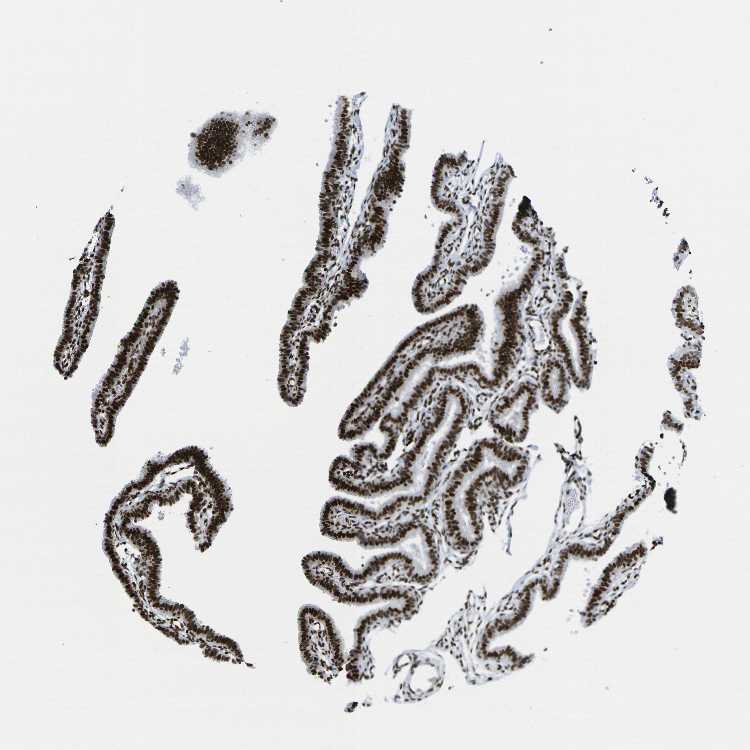

FALLOPIAN TUBE - Antibody stainingi

Antibody staining in the annotated cell types in the current human tissue is reported as not detected, low, medium, or high, based on conventional immunohistochemistry profiling in selected tissues. This score is based on the combination of the staining intensity and fraction of stained cells.

Each image is clickable and will lead to virtual microscopy that enables deeper exploration of all samples and also displays staining intensity scores, fraction scores and subcellular localization as well as patient and tissue information for each sample.

Antibody HPA068431Antibody CAB012235

Glandular cells HighHigh